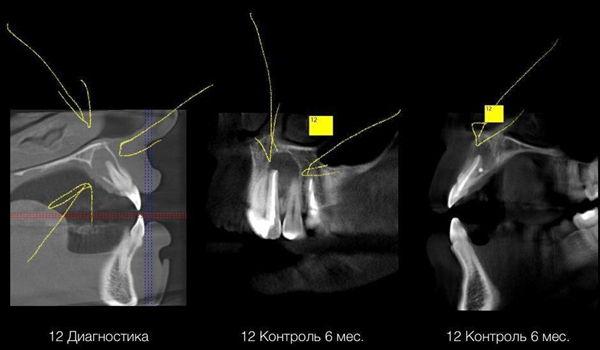

С резцом повезло меньше. Если честно, то мы уже планировали его на удаление: настолько велика была гнойная полость на верхушке корня. На левой фотографии видно, что даже кость разрушена, а содержимое кисты отграничивает только слизистая со стороны нёба. Зуб, по сути, держится только в районе своей шейки и на боковой поверхности, а остальное уже было съедено инфекцией. К сожалению, после лечения канала мы не добились полного заживления и киста осталась, хоть и немного уменьшилась.

Поэтому мы решили попробовать спасти зуб более радикальными методами — просто взяли и удалили верхушку корня, попутно вычистив весь очаг вручную. Тут уже занимался не стоматолог-терапевт, а хирург. Чуть позже расскажу, как это выполняется.

В результате удалось сохранить девушке её резец, а костные структуры полностью восстановились после операции.

Я уже говорил, что нам пришлось выполнить небольшую операцию для спасения резца. Несмотря на то, что мы вылечили и запломбировали боковой резец, спустя шесть месяцев киста не исчезла. Так получилось из-за огромных размеров очага и невозможности его ликвидировать, просто вычистив корневой канал.

Для того чтобы решить проблему, мы пошли на резекцию верхушки корня. При этом стоматолог-хирург получает доступ к корню с обратной стороны, через кость. Под анестезией осторожно откидывается слизисто-надкостничный лоскут, перфорируется кость, и хирург получает возможность непосредственно удалить проблемную верхушку корня и специальным инструментом вычистить всю полость. Затем доступ в корневой канал закрывается пробкой из специального материала (белое пятнышко у верхушки корня). Всё промывается антисептиком, после чего ушивается.

Очаг инфекции был устранён, есть признаки восстановления костной ткани. Зуб, который изначально предполагался под удаление, удалось спасти, хотя шансы на это были не самые лучшие.